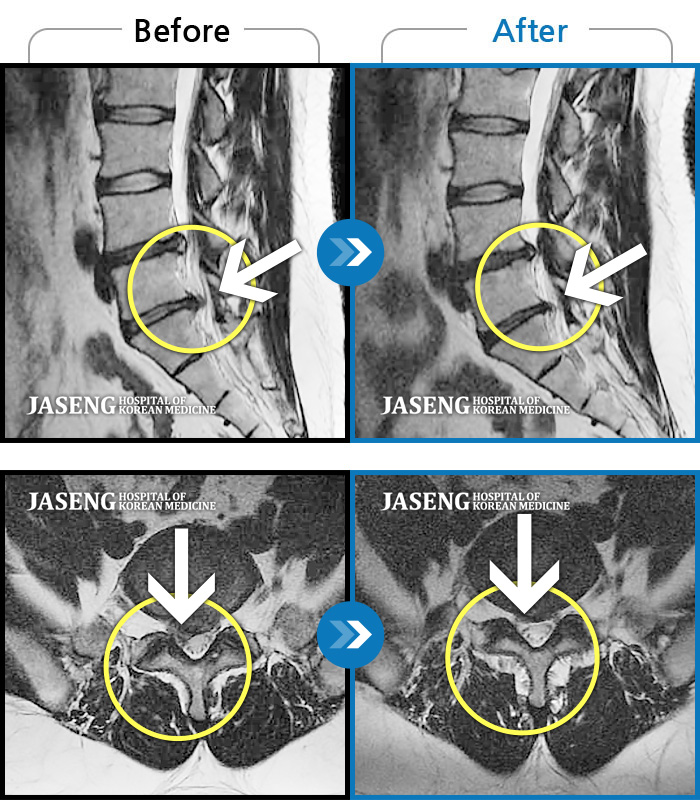

허리디스크

잠실 · 한상욱 원장

허리, 우측 엉치와 다리 후면 및 발끝까지 저림과 통증이 심하고 힘까지 빠진다.

촬영시기

2022.06.15 ~ 2022.11.11

2022.12.02